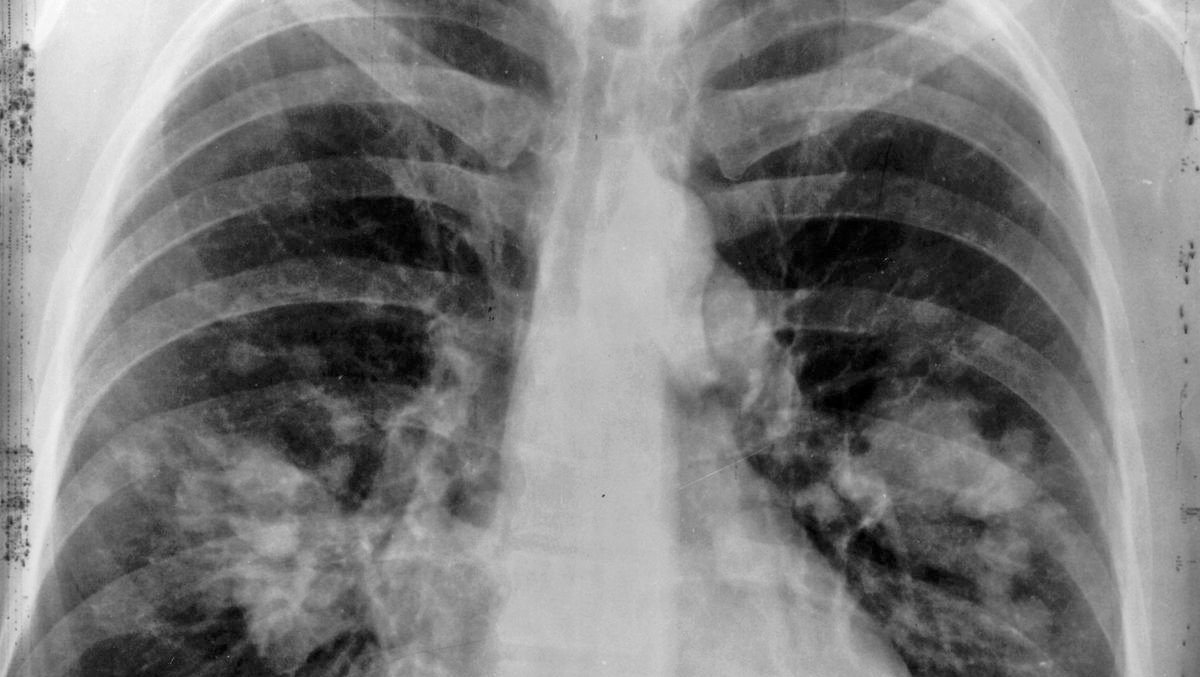

Kadınlarda en çok meme, rahim ve kalın bağırsak kanseri; erkeklerde ise en çok akciğer, prostat, mide ve kalın bağırsak kanserleri görülmektedir. Tüm kanserlerin %16'sı, tüm kanser ölümlerinin %28'i erkeklerde %35, kadınlarda %19 akciğer kanseri nedeniyledir. Akciğer kanseri büyük ölçüde sigara kullanımı ile ilişkilidir; kadınların sigara tüketimindeki artışlar, akciğer kanserlerinin de artmasına neden olmaktadır.

- Solunum sistemi belirtileri Bronş obstrüksiyonu yapan tümörler dispne, pnömoni

- Akciğer parenkiminin yoğun invazyonunda solunum hacmi azalması

- Plevra infiltrasyonunda ağrı